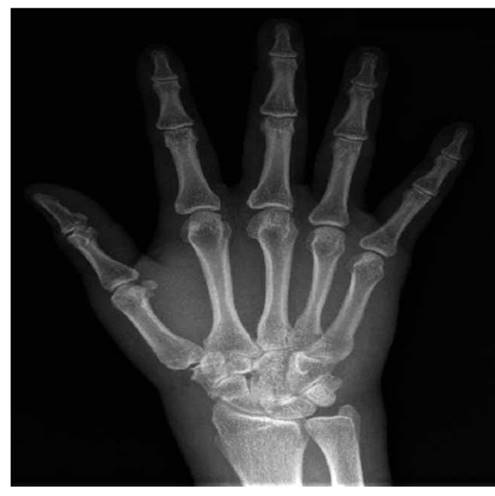

Los paraclínicos iniciales muestran leucocitosis con neutrofilia y PCR (Proteína C reactiva) elevada, resto de límites normales (Ver tabla 1). Se amplían estudios con perfil infeccioso, metabólico y autoinmune dentro de límites normales excepto por un factor reumatoide positivo; radiografía de tórax dentro de límites normales y radiografía de manos sin alteraciones óseas con edema de tejidos blandos (Ver imagen 2). El rastreo microbiológico solicitado al ingreso da preliminar a las 29,7 horas de morfología indeterminada, con cubrimiento antibiótico empírico con ampicilina sulbactam a dosis de 3 gramos cada 6 horas.

Imagen 2: Radiografía de mano derecha. No lesiones óseas, ni articulares, se observa edema de tejidos blandos a nivel de metacarpofalángicas.